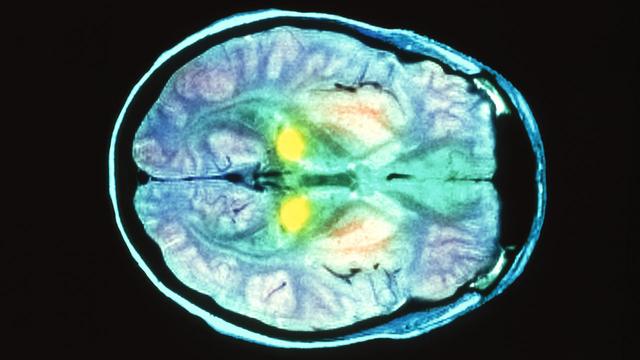

因为死亡原因尚不清楚,科学家冷冻了她的大脑,并将其浸泡在化学防腐剂甲醛中。三天后,甲醛可以去除氨基酸;“固定”;科学家们一起将大脑切片,并将其浸泡在石蜡中,在显微镜下拍照,并将所有数据存档,以备日后研究之用

几年后,第二组科学家重新提取这些切片组织进行研究,稀释干燥的组织并将其注射到小鼠体内。令人惊讶的是,尽管对死者的脑组织进行了标准灭菌处理,但在注射的8只小鼠中,有4只仍有与死者相同的症状

朊病毒复杂而稳定的结构赋予它们超自然的生存能力。朊病毒α螺旋占3%,β折叠占43%,这使得蛋白质高度抗降解

在病理变化过程中,朊病毒聚集成链接的淀粉样蛋白也可以保护它们免受攻击。淀粉样蛋白通常沉积在由组织引起的慢性疾病中,如;胶水“;它还依附于手术器械,并通过了标准的灭菌程序。